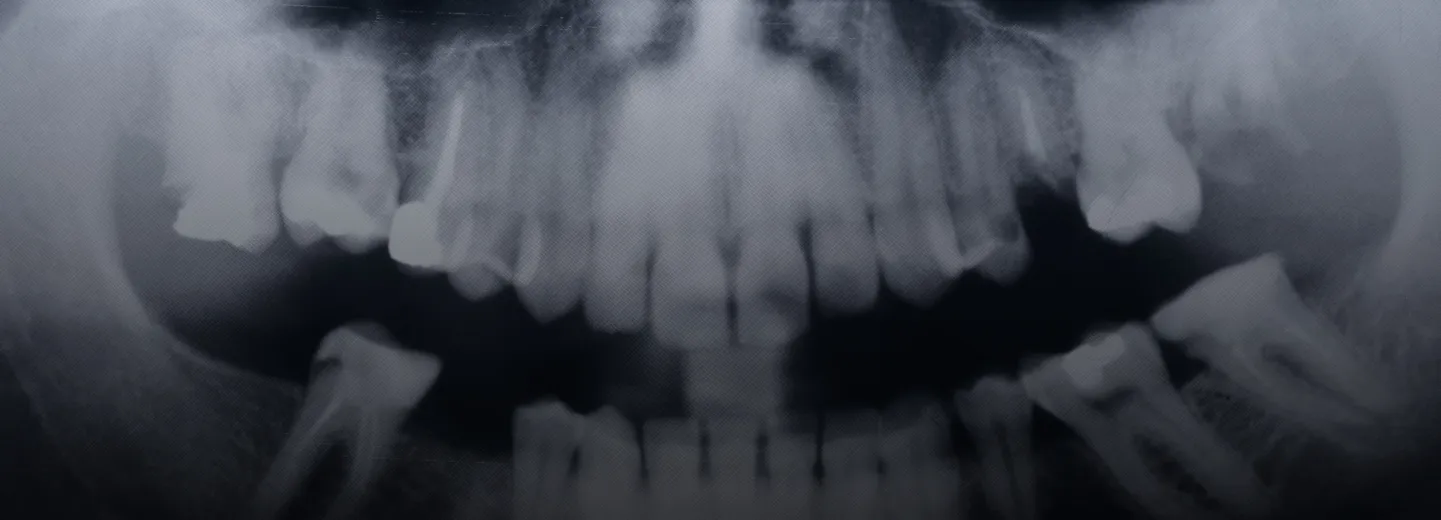

- Teeth Structure: Modern humans typically have smaller teeth and jaws compared to their prehistoric ancestors. Dental issues such as malocclusion (misaligned teeth) and impacted wisdom teeth have become more common due to the reduced jaw size.